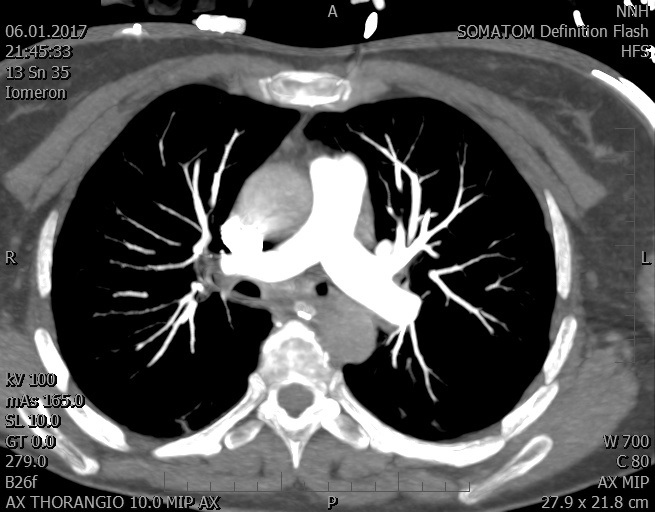

Video 2 - Echokardiograficky byla zjištěna těžká dysfunkce dilatační levé komory s nezvětšenou pravou komorou.Pro nejasnou příčinu zástavy jsme provedli i vyšetření výpočetní tomografií (CT), které vyloučilo plicní embolizaci (série 1 - soubory na konci článku). V den přijetí při přetrvávající oběhové nestabilitě byla nemocná opakovaně defibrilována pro fibrilaci komor se stabilizací rytmu po podání amiodaronu a mesocainu. Dle hemodynamických měření se jednalo o těžký kombinovaný šok. Vstupní laboratorní vyšetření bylo bez větších pozoruhodností. Posléze jsme doplnili anamnézu od příbuzných a zjistili, že pacientka užila do dvou hodin před srdeční zástavou první tabletu amoxicilinu na lehký respirační infekt. Při nevýtěžnosti vstupních vyšetření a nových anamnestických informacích jsme doplnili 14 hodin po kolapsu vyšetření koncentrace tryptázy v séru, která byla extrémně zvýšena (tabulka 2), což nás vedlo k podezření na anafylaxi.